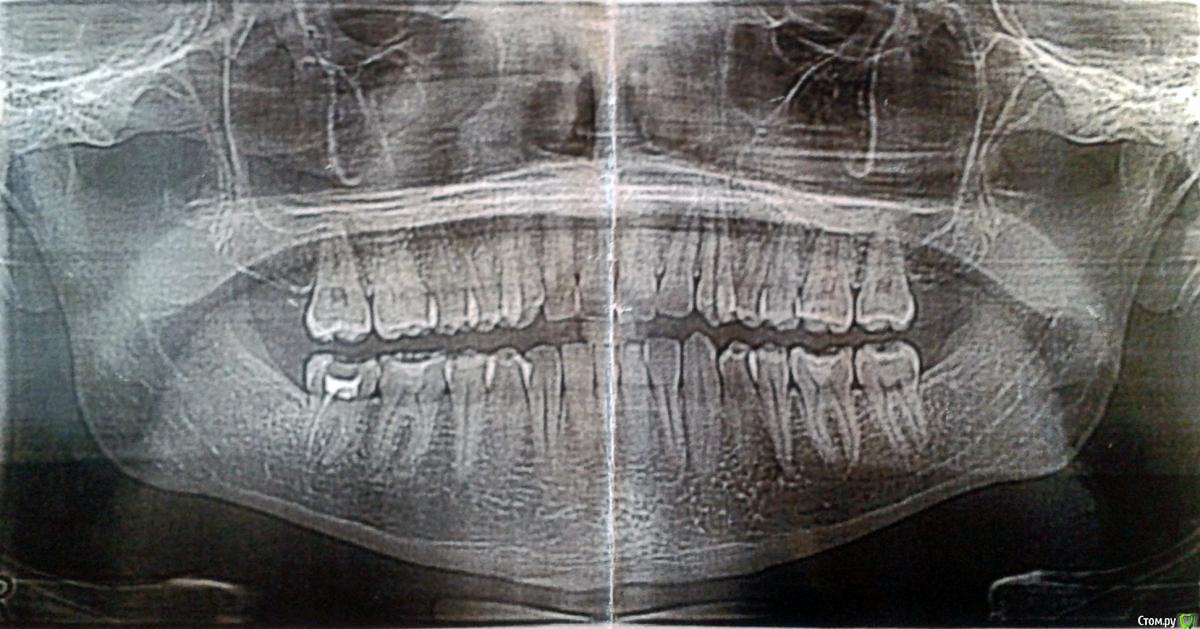

6467t655576 Опубликовано 25 января, 2019 Поделиться Опубликовано 25 января, 2019 (изменено) Здравствуйте.Уже несколько лет беспокоят чередующиеся онемение, боль, непонятные пульсации справа, в районе нижней семерки, хотя дискомфорт нередко охватывает и верхние, и до пятёрок. Удалил все кривые восьмерки - не то. Чуть больше года назад лечил 47, но как-то лучше не стало. Врачи отправляли к неврологу, недавно увидели небольшое воспаление и кололи линкомицин - положительный результат держался меньше недели. На последней оптг узрели кисту, требующую немедленного лечения.Прошу вашего мнения, что видно на снимках, и как с этим бороться (резать десну, "перепроходить" каналы, или правда неврология)?Снимок 47 совсем свежий (дважды, не знаю, какое фото лучше), оптг снимок и фото с монитора в рентгенкабинете около месяца, старая оптг сделана летом. Изменено 25 января, 2019 пользователем 6467t655576 Ссылка на комментарий

kramer Опубликовано 25 января, 2019 Поделиться Опубликовано 25 января, 2019 Мне кажется, здесь картина неврита тройничного нерва и накладывающиеся на него симптомы периодонтита ("киста") зуба 47. Две отдельные проблемы, решать их надо отдельно. 1 Ссылка на комментарий